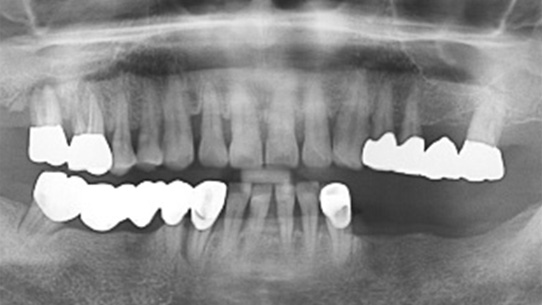

심한 염증과 기존 보철물의 오염상태가 심해 다른 병원에서 임플란트 17개 진단을 받고 내원, 특히 앞니부분의 치조골이 많이 약해져 흔들림이 심하여 바로

치주치료를 시행하였습니다. 치주치료 2주 후 앞니 잇몸이 개선되어 발치 하지 않고 교정 유지장치를 이용하여 흔들림을 보완하였습니다.

오염된 보철물을 제거하고 임플란트 11개를 식립하였습니다.

심한 염증으로 치아가 흔들리는 상태

앞니 흔들림을 보완하는 유지장치 부착